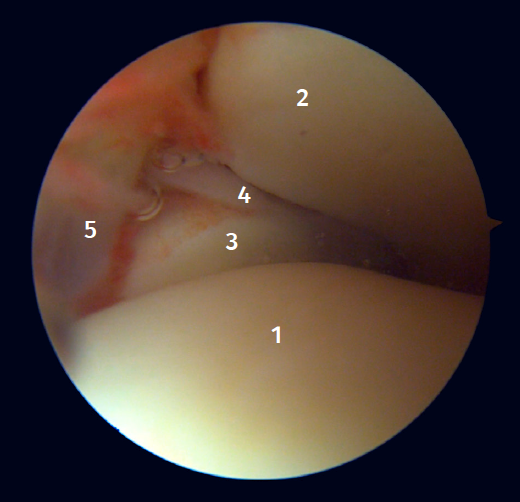

Figura 2. Visión artroscópica anterolateral del tobillo derecho. 1: cúpula astragalina; 2: cara anterior de la tibia; 3: peroné; 4: fibras distales del ligamento tibioperoneo anterior; 5: ligamento peroneo-astragalino anterior.

Figura 3. Visión artroscópica anterolateral de un tobillo derecho al introducirnos en la tibioastragalina. 1: cúpula astragalina; 2: cara articular de la tibia; 3: peroné; 4: articulación tibioperonea distal; 5: fibras distales del ligamento tibioperoneo anterior.